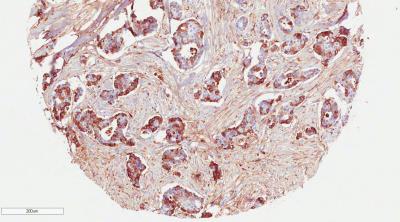

High expression of COMP in breast cancer cells, seen here in brown, is associated with poor clinical prognosis for the patient. Cancer cells expressing COMP become more invasive and change their metabolism, which allows them to survive better and spread to other organs.